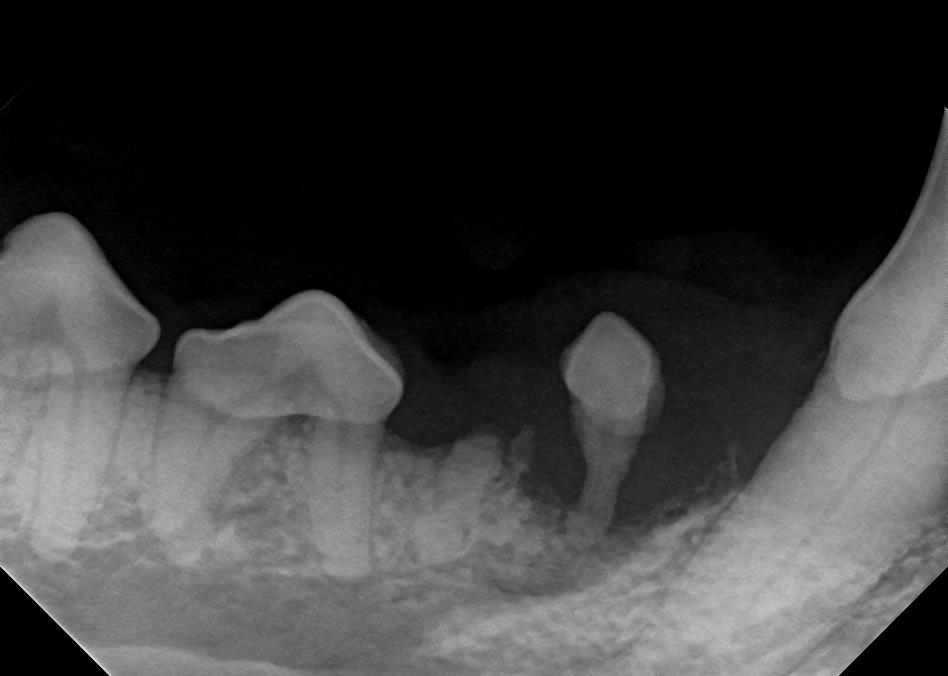

Dental X-Rays

Click on an image to learn more!